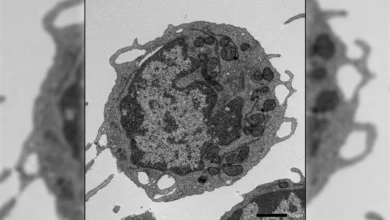

Many cells in the body, especially those that line blood vessels, are covered by a dense outer layer called the glycocalyx. This coating is made up of complex sugar molecules that form a gel-like layer on the cell surface. It serves several important functions, including protecting blood vessel walls from physical stress and chemical damage. In recent years, researchers have also discovered that the glycocalyx helps regulate how immune cells travel through the body.

Previously, scientists believed that changes in the glycocalyx of blood vessel walls were mainly responsible for allowing immune cells to pass from the bloodstream into surrounding tissues. This new study challenges that view. The team found that immune cells themselves have their own glycocalyx and actively shed part of this sugar layer to move out of the blood and into inflamed skin in conditions such as psoriasis.